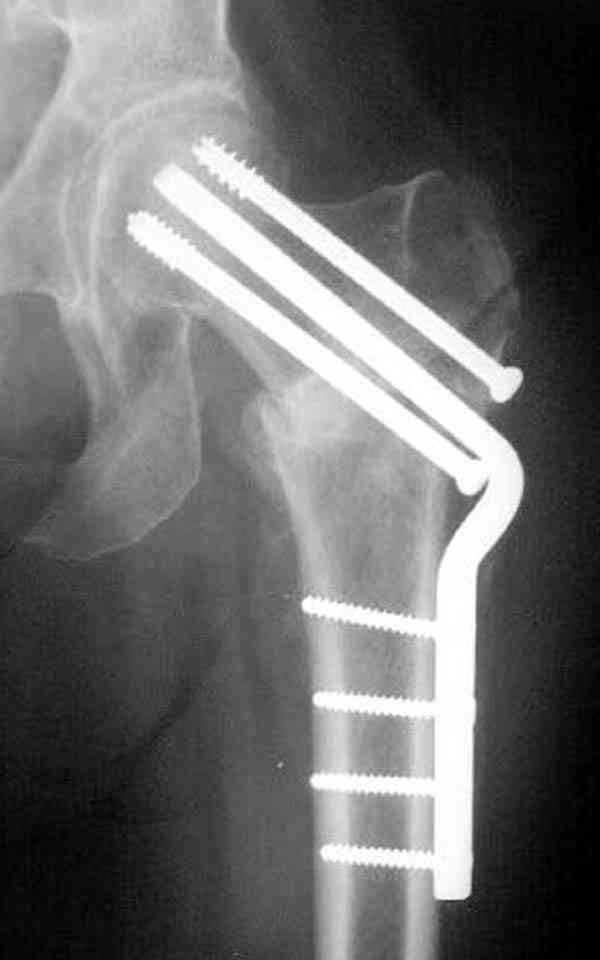

Коллега Челноков прав, здесь еще имеется риск перелома за счет ослабления латерального кортекса. Во время установки канюлированных шурупов за редким исключением спица вводится с одного раза, множественные попытки ослабляют латеральный кортекс, что станет источником перелома в этом месте.

В идеале для профилактики рефрактуры шурупы надо вводить не больше, чем под 130 градусным углом и не ниже уровня малого вертела.

Насчет биомеханических преимуществ одного шурупа тоже возникает вопрос. Если придерживаться канонов механики, для перелома шейки необходимо 3 паралельных шурупа, расположенных ближе к кортикальному слою шейки.

Здесь случай перелома из-за ослабления латерального кортекса через 3 недели после операции на шейке. Шурупы были установлены под большим углом, слабый латеральный кортекс не выдержал нагрузку.